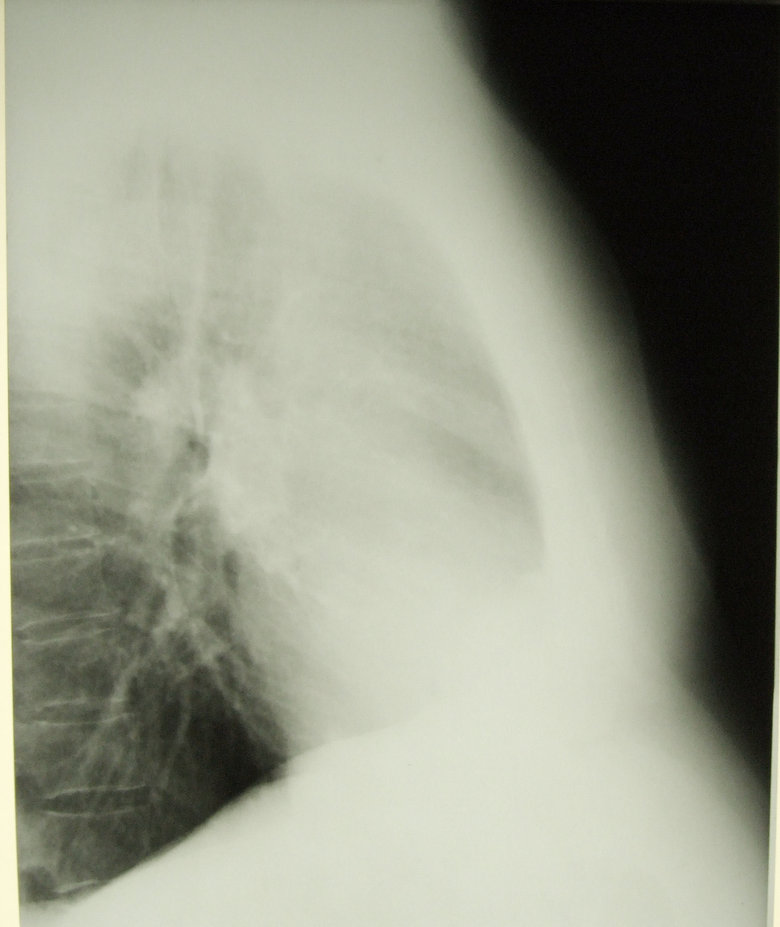

непарная вена + добавочная доля непарной вены правого легкого.

Обсуждалось здесь viewtopic.php?f=24&t=2594